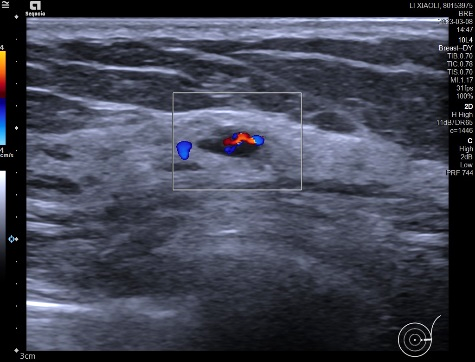

常规超声显示,左乳4点处可见一个低回声实质团块,诊断为乳腺MT(BI-RADS 4C)。左乳外上近3点处另可见一个6×3mm的低回声实质小结节,边界尚清晰,未见明显包膜,内回声分布尚均匀,与MRI显示的位置一致。

彩色多普勒超声显示,该结节内部可见较丰富的短线状彩色血流信号。

然而剪切波超声弹性成像VTIQ进一步评估发现,该结节质地较软,内部呈蓝绿色。